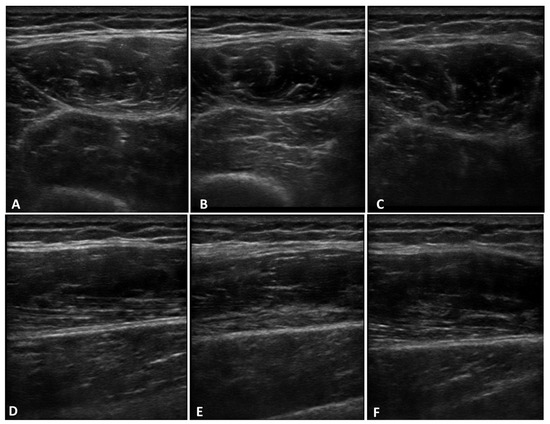

Figure 4. US images of deep fascia of thigh on transversal (AC) and longitudinal (DF) scans at three different probe inclination angles: 0° (A,D), −5° (B,E), and +5°(C,F).

The comparison between the three probe inclination angles (0°, −5°, and +5°) on both transversal and longitudinal scans showed a statistically significant difference in the echogenicity (Figure 3 and Figure 4).

The comparison between the three probe inclination angles (0°, −5°, and +5°) on both transversal and longitudinal scans showed a statistically significant difference in the US thickness (Figure 4 and Figure 5).